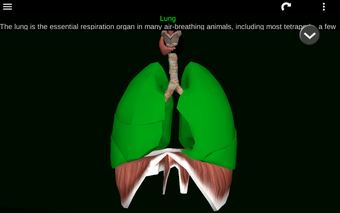

此应用程序显示人体器官的三维模型和所有器官的描述。

您可以触摸每个器官,如心脏、大脑、肺、生殖系统、肝脏、肠道、卵巢、睾丸、胃、肾脏等。

它对所有人都有用,甚至对学生也有用,因为每个解剖器官都以不同的颜色显示。